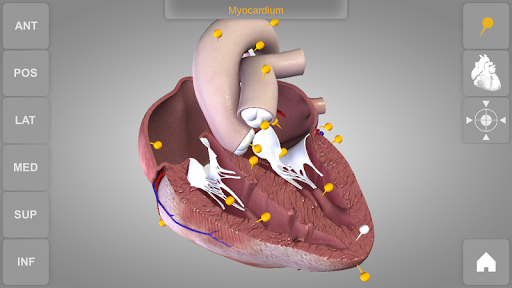

Heart 3D Atlas of Anatomy allows you to rotate a highly realistic 3D heart model as it was in your hands.

The human heart anatomical 3D model is revolvable in any direction giving a 360° view of the object.

User can choose external view or section view. Moreover, the names of specific anatomical areas can be shown touching the related pins (available in the full version only).

Heart app is part of 3D Atlas of Anatomy collection, a human anatomy reference atlas for tablet and smartphone devices. The 3D medical models in these apps are similar to classic real plastic models but with the great benefits to be always available on your portable devices when you need them and occupy no physical space.

These apps can be of great help for students of medicine or to anyone who needs to study human anatomy shape in detail and from any angle. Immediacy and simplicity together with high quality are distinctive features of the app.